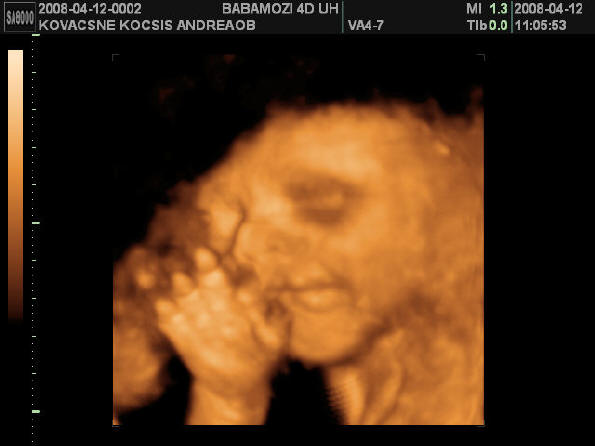

És egy tappancs 2008.03.08 19:45